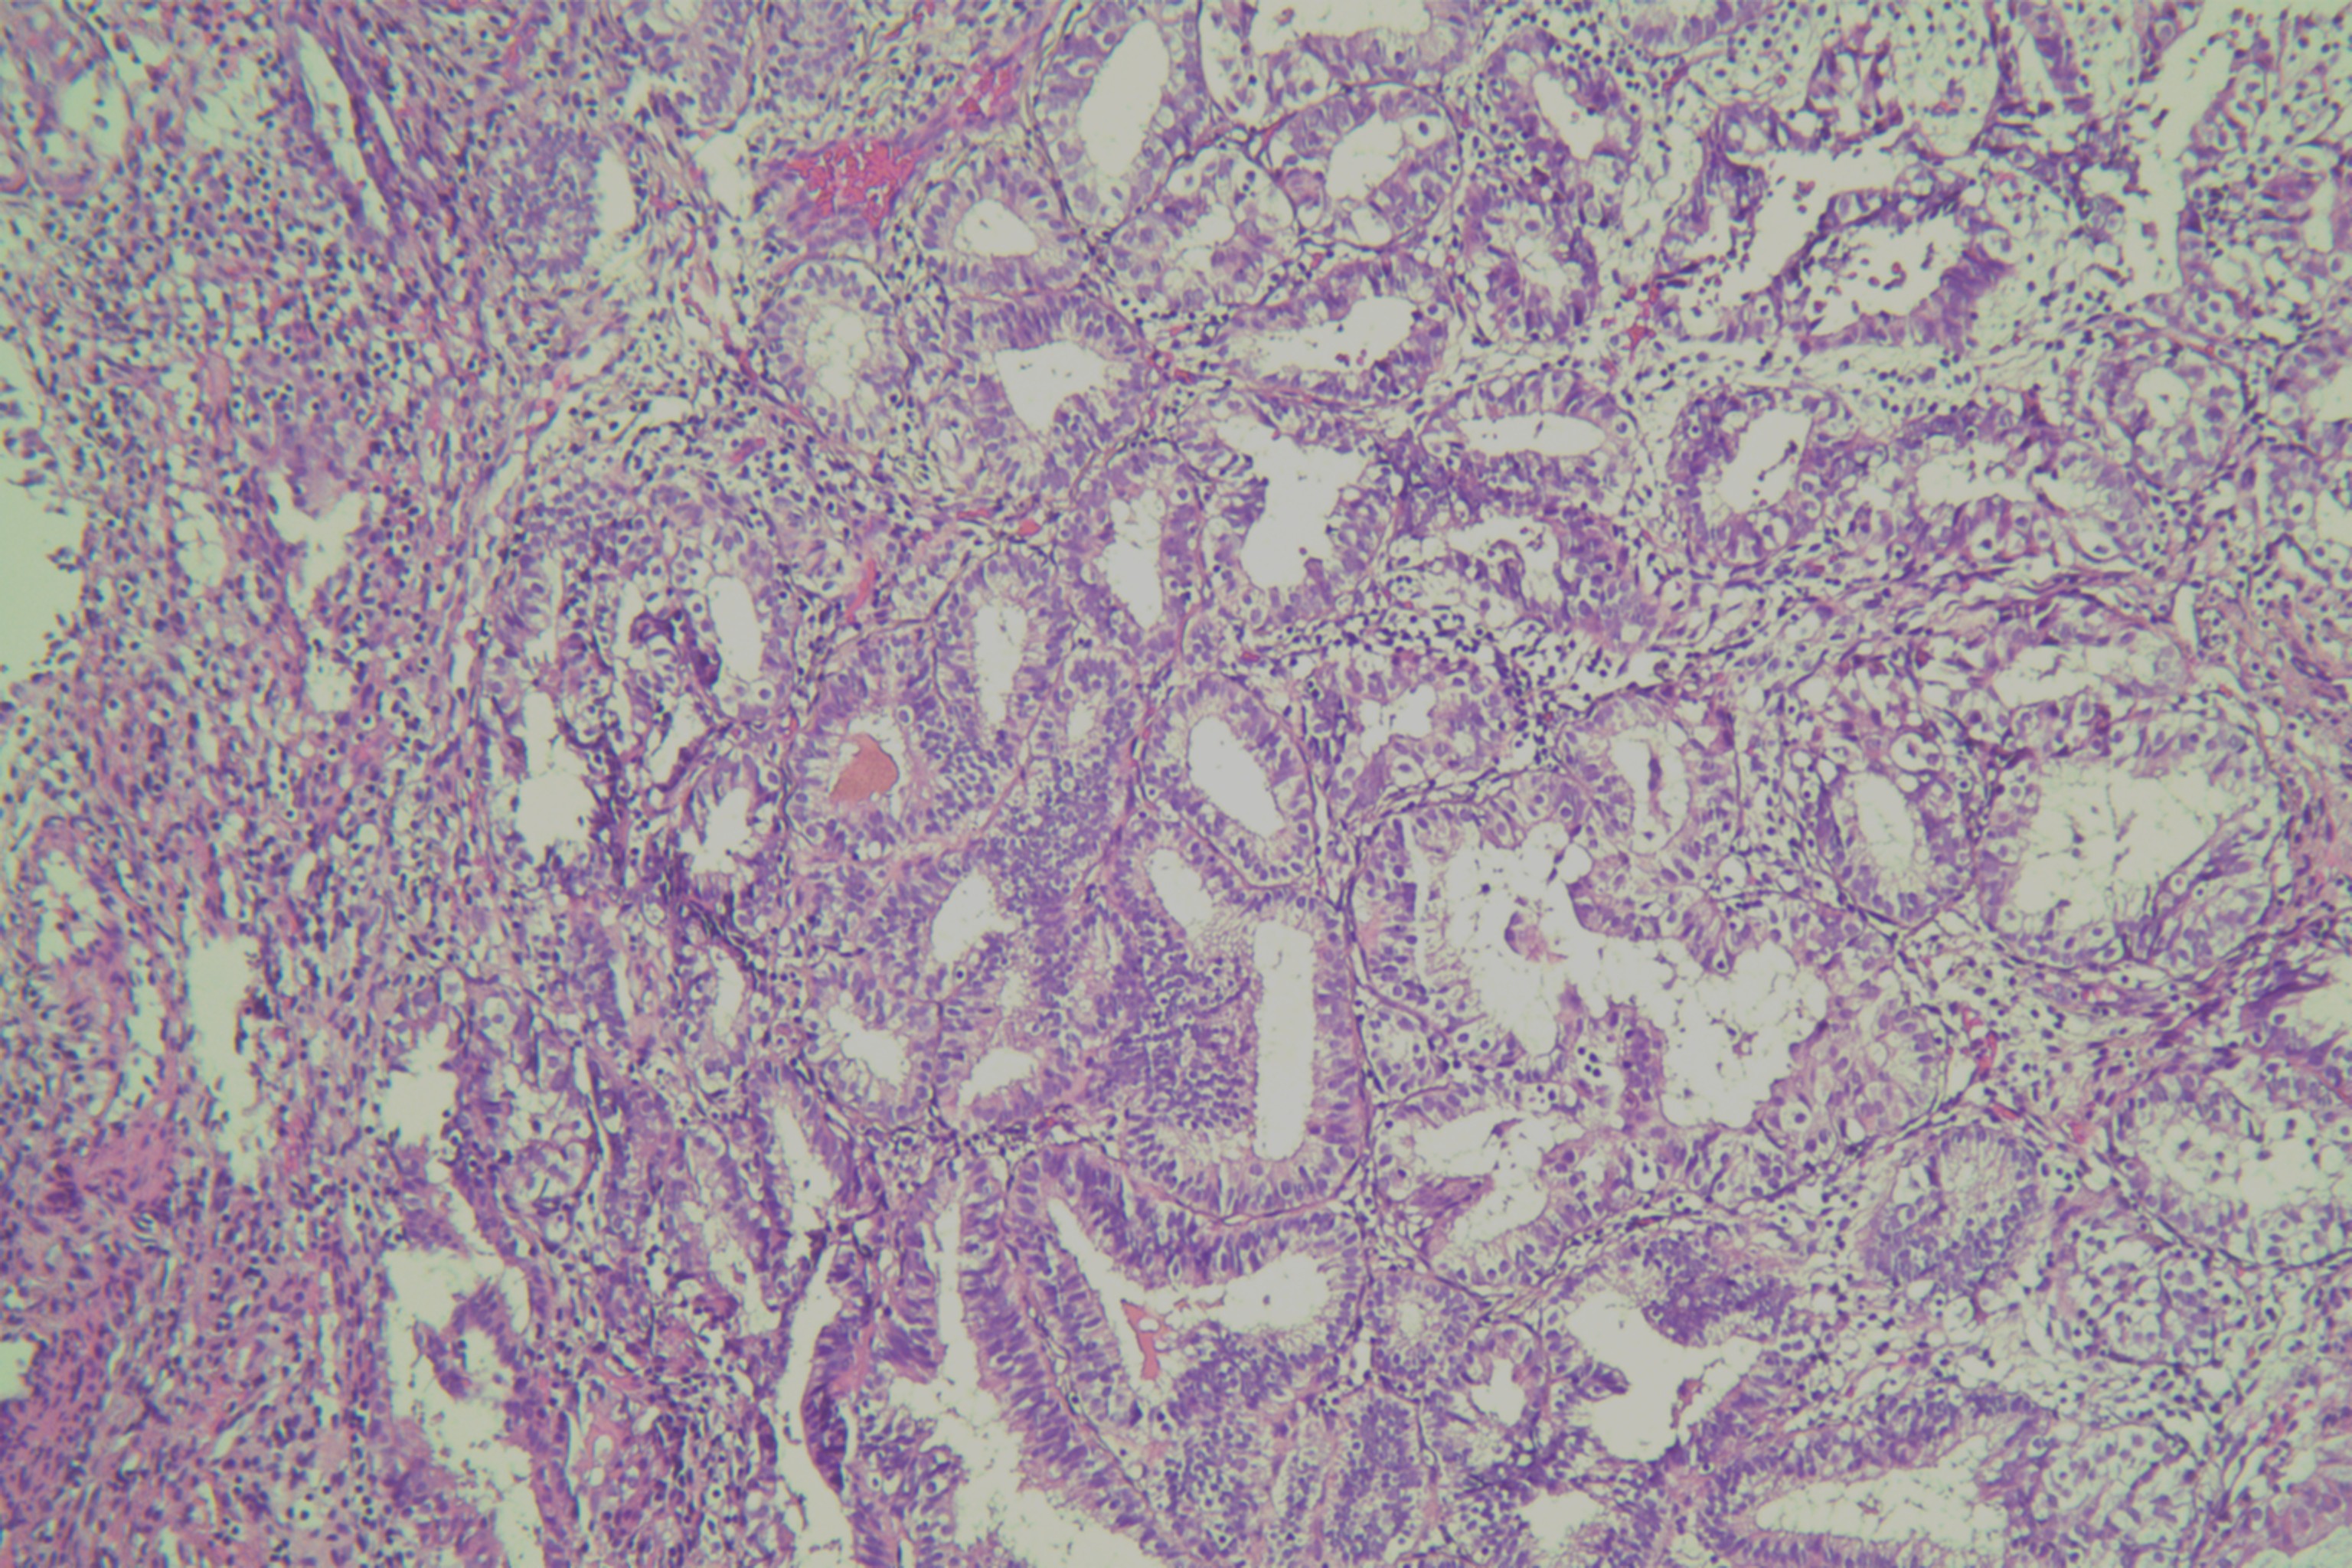

子宫内膜有无非典型性?

月经紊乱1年余,子宫增厚11月

宫腔刮出物

2.8*2.3*0.5cm灰红碎组织一堆。

嗜酸性乳头状化生。

未见非典型增生考虑为子宫内膜单纯性增生部分区域腺体呈复杂性增生(图6)伴部分腺体呈嗜酸性乳头状化生

局灶非典型性增生伴嗜酸性乳头状化生